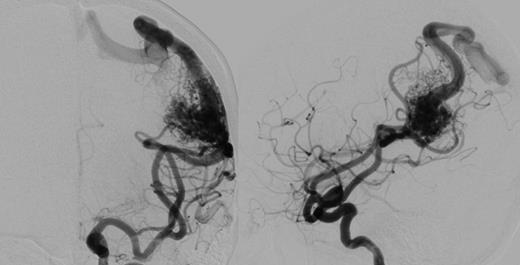

A 56-year-old female presented following a single tonic clonic seizure. Neurological examination was unremarkable. An MRI scan revealed a left posterior frontal parafalcine meningioma with vasogenic oedema in the precentral gyrus with a localized mass effect. In addition, there was a 2.6-cm left parietal AVM located in the left angular/supramarginal gyrus (Fig. 1). There was no evidence of prior haemorrhage. Cerebral angiography confirmed the arterial supply to be predominantly from enlarged parietal and angular branches of the left middle cerebral artery. Venous drainage was superficial into an enlarged vein of Trolard towards the superior sagittal sinus (Fig. 2).

Cerebral angiogram, antero-posterior (left) and lateral (right) revealing a 2.6 × 2.6 × 3.4 cm sulcal type AVM in the left parietal region. Arterial supply is from enlarged parietal and angular branches of the left middle cerebral artery. Venous drainage is superficial into an enlarged vein of Trolard towards the superior sagittal sinus.